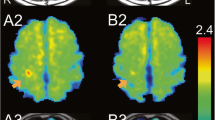

For the specific imaging of astrocyte, acetate is expected to be useful as a selective marker of astrocytic energy metabolism [18, 19]. 14C-acetate is rapidly incorporated into glutamine via glutamate by glutamine synthetase localized in astrocytic cells [20]. Hosoi et al. demonstrated that 14C-acetate uptake is dramatically decreased in a 3-min ischemia and reperfusion model, indicating that the metabolic and functional impairment of astrocytes continues after the restoration of CBF [21]. 11C-labeled acetate could be a promising PET tracer for the evaluation of astrocytic metabolism in human studies (Fig. 19.6).

Qualitative and quantitative 11C-acetate PET imaging for astrocytic energy metabolism. (a) An averaged 11C-acetate PET image (from 0 to 40 min) and (b) an averaged Kmono image in a healthy volunteer. The energy metabolism evaluated using the Kmono image was different from the normal oxygen metabolism evaluated using the CMRO2 image (c)